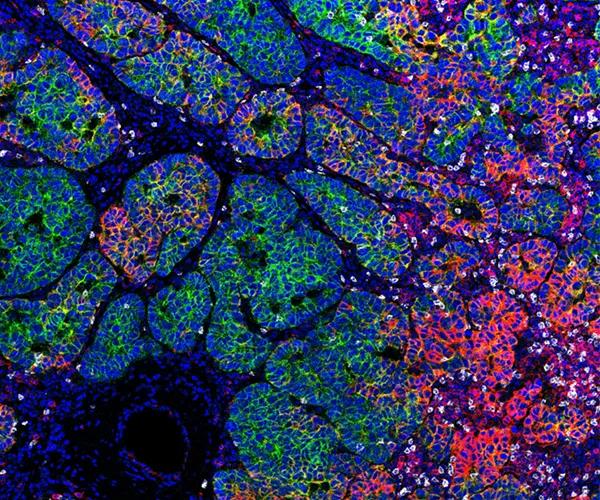

Low-passage samples retain the heterogeneity and fidelity of human cancers. Engrafted tumors derived from a patient with a bladder urothelial papillary carcinoma demonstrate high concordance of tumor morphology, compared to low passage PDX tumor TM00015.

Figure C) Tumor cells of patient origin within the xenograft-stained positive using an anti-human antibody for Ki67.